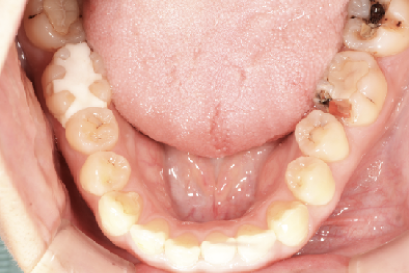

術前

術後

年代、性別

10代、女性

職業

学生

主訴

歯並び相談

部位

抜歯を併用してのインビザラインによる全顎矯正

治療期間

2年

矯正費用

95万円

施術説明

前歯が突出感と、下歯がガチャガチャしていることを改善したいということでした。マウスピース矯正は抜歯を伴う矯正は難しいという意見もありますが、適切に診査・診断を行い対応すれば問題ありません。本症例では、上下2本ずつ合計4本の抜歯を行い、スペースを作ることで、上記の問題を矯正で改善しました。非常に綺麗な歯並びになり、非常に喜んでもらえました。

副作用・リスク

なし